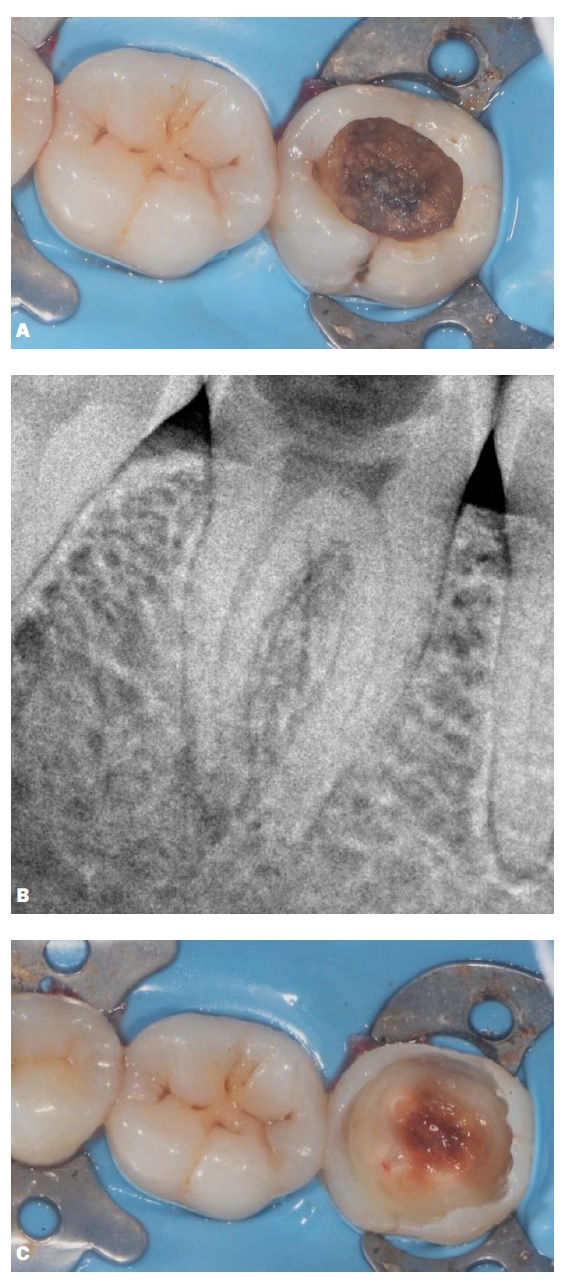

1. Anamnesis y Diagnóstico

Paciente masculino de 37 años de edad, sin antecedentes sistémicos relevantes, acude a la consulta por sintomatología dolorosa provocada ante estímulos térmicos en el cuadrante inferior izquierdo (Figura 2). Al examen clínico, se observa una lesión de caries oclusal extensa en la pieza 3.7. Las pruebas de sensibilidad térmica (frío) desencadenan un dolor agudo con ligera persistencia, mientras que las de percusión y palpación resultan negativas. Radiográficamente, se confirma una lesión radiolúcida compatible con caries dentinaria profunda con compromiso inminente de la cámara pulpar, pero con el espacio de ligamento periodontal conservado. El diagnóstico se establece como pulpitis moderada.

Se optó por una Terapia de Pulpa Vital (Pulpotomía Total) en lugar de un tratamiento endodóntico convencional, fundamentado en la capacidad regenerativa del complejo dentino-pulpar y la disponibilidad de materiales bioactivos de última generación. El objetivo primordial fue mantener la vitalidad de la pulpa radicular y aprovechar su potencial regenerativo.

Aislamiento y Acceso: Tras la administración de anestesia local, se realizó aislamiento absoluto con dique de goma y desinfección del campo con peróxido de hidrógeno al 3% y luego con clorhexidina 0,2%. Se inició la remoción de la caries dentinaria en la pieza 3.7 con una fresa de un único uso, estéril y con alta velocidad.

Abordaje Pulpar: luego de eliminar por completo la caries dental, se procedió a la escisión completa de la pulpa cameral utilizando fresas de diamante de alta velocidad bajo irrigación profusa.

Control de Hemostasia: utilizando una torunda de algodón embebida en NaOCl al 2.5%, se logró la hemostasia en un tiempo inferior a los 6 minutos, confirmando la viabilidad del tejido pulpar radicular para el procedimiento.

Protección Bioactiva: Se colocó Biodentine™ (Septodont, Francia), un cemento de silicato de calcio de alta pureza, adaptándolo sobre el remanente pulpar para garantizar su bioactividad y un posterior sellado hermético, según proporciones descritas anteriormente.

4. Restauración y Seguimiento

Tras el fraguado inicial del material bioactivo, se realizó un grabado ácido selectivo del esmalte y se procedió a una reconstrucción biológica no anatómica utilizando el sistema de resina dual ParaCoreÒ (Coltène/Whaledent AG). Este enfoque asegura un sellado coronal inmediato, factor crítico para el éxito a largo plazo.